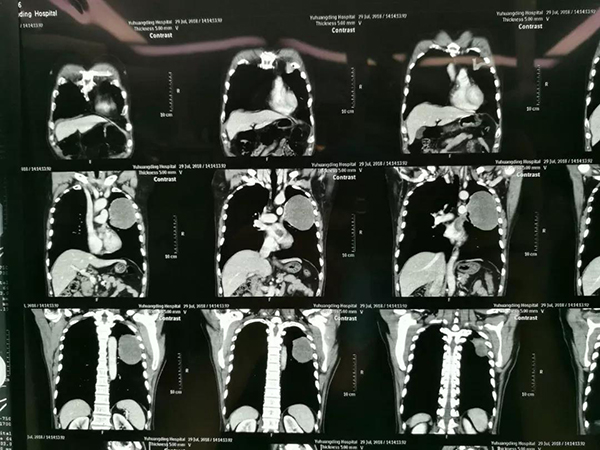

患者郭某某,男,66岁,查体发现左肺部肿瘤1年余。1年前患者健康查体时发现左肺部占位性病变,当时未予治疗。今年再查体发现病变较前明显增大。2018年7月29日在烟台当地医院进行胸部强化CT显示左肺上叶巨大肿瘤,大小约12cm×10cm×8 cm,肿瘤与左侧胸壁关系紧密,且肿瘤侵及左上肺静脉并左心房内癌栓形成。因肿瘤巨大且心脏受侵,左心房内癌栓有随时脱落致死危险,当地医院表示难以手术治疗,患者及家属怀着求生的一线希望,以及对山东省立医院的信任,千里迢迢前来我院就诊。